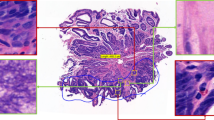

BreastPathQ dataset consists of 69 WSIs, where each WSI is annotated for the tumor bed outline. By definition, patches extracted from outside of the tumor bed region are considered as completely cancer-free. We sample patches from outer extents of each WSI and collect a total of 1.4 million images. Then, we sample 21 thousand images randomly or by clustering. For clustering, we use features (∈R1280) generated by EfficientNet-B0 model trained on ImageNet12. Specifically, we use features corresponding to each image obtained by 2d-average pooling of the final layer of the network prior to the fully-connected classification layer (also called as the pre-activation). We then cluster 1.4 million feature vectors into three thousand clusters using the mini-batch K-means algorithm and select seven instances from each cluster. To find the optimal cluster size, we use the Elbow method principle. We run K-means with cluster sizes {1000, 1500, ..., 10000}. 2500 clusters achieve an explained variance of 67.1%, 3000 clusters is 83.3%, and 5000 is 91%. Examples of sampled images from both random and K-means sampling strategies can be viewed in Fig. 1.

Negative mining with random sampling versus feature based K-means clustering from whole-slide images. Both figures are extracted from actual experiments. (a) Random sampling (b) K-means sampling. In (b), we show the three samples closest to the centres of six randomly selected clusters for illustration.